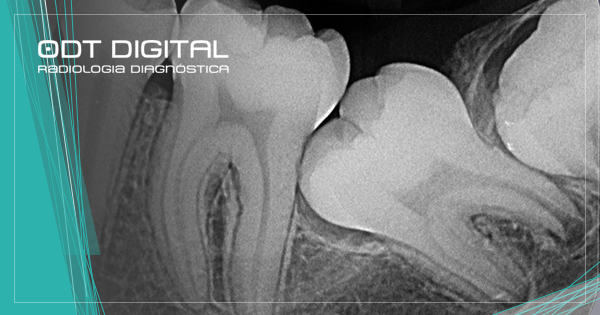

A radiografia periapical analisa a estrutura de um até três dentes contínuos, desde a coroa até as raízes, além de